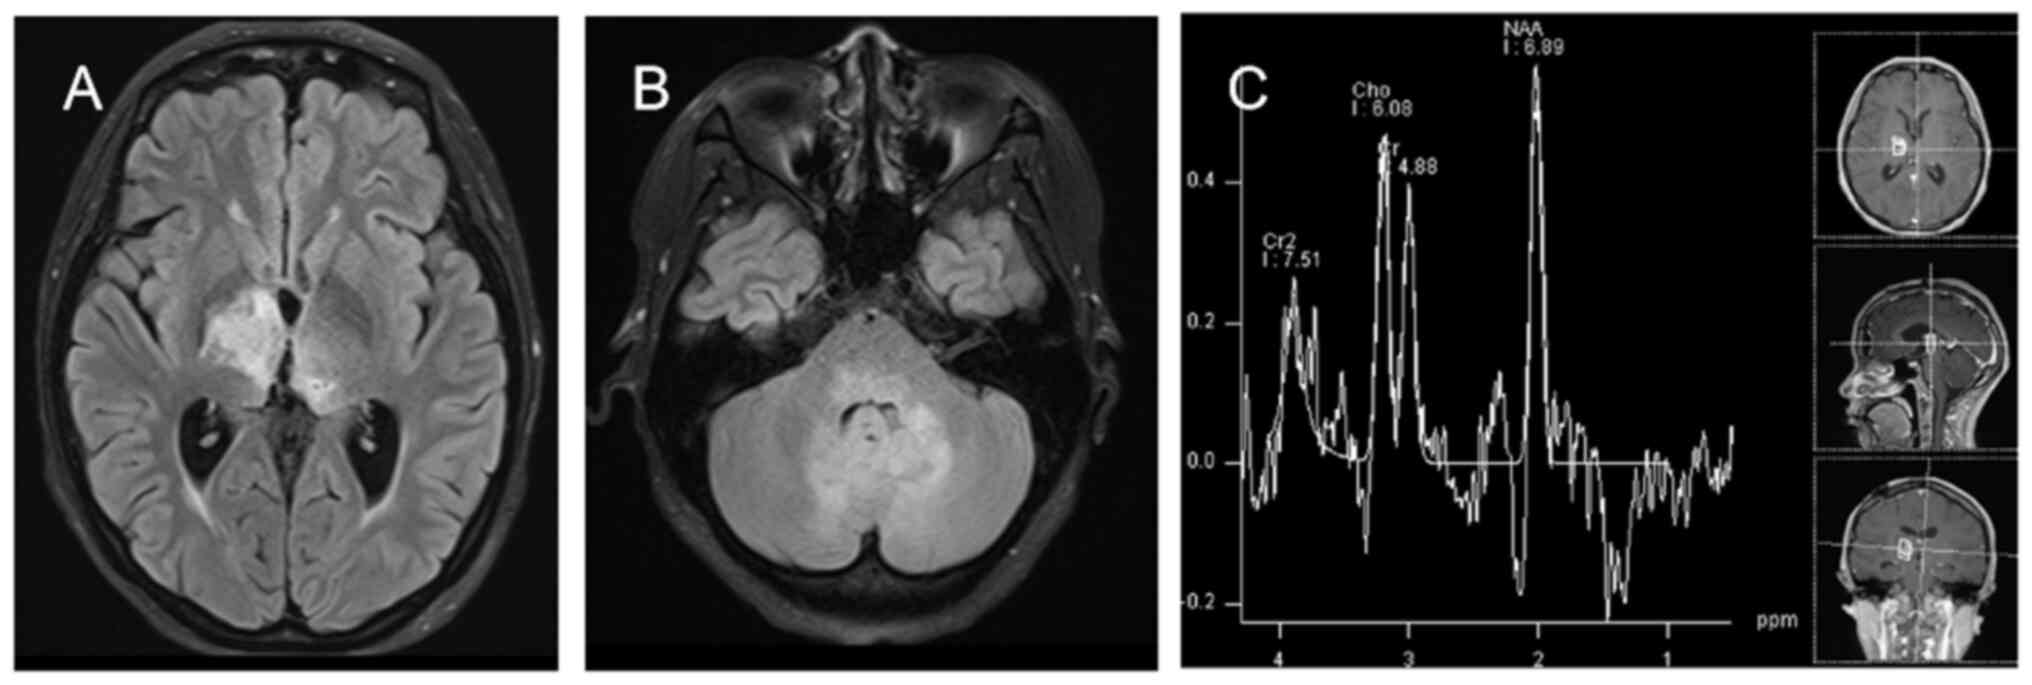

Personalized combination therapy for diffuse midline glioma: A case report

The present study aimed to analyze the efficacy of personalized combination therapy for patients with H3K27M mutant diffuse midline glioma (DMG) so as to explore new treatment options for further clinical research. The clinical data and prognosis of a patient with H3K27M mutant DMG are summarized and discussed in the context of the relevant literature. The patient was a 20‑year‑old female diagnosed with DMG treated with a combination of surgery, radiotherapy, chemotherapy, electric field therapy, immunotherapy and targeted therapy. An overall survival time of 28 months was achieved. In summary, personalized treatment strategies are expected to provide longer‑lasting survival benefits for patients with DMG.